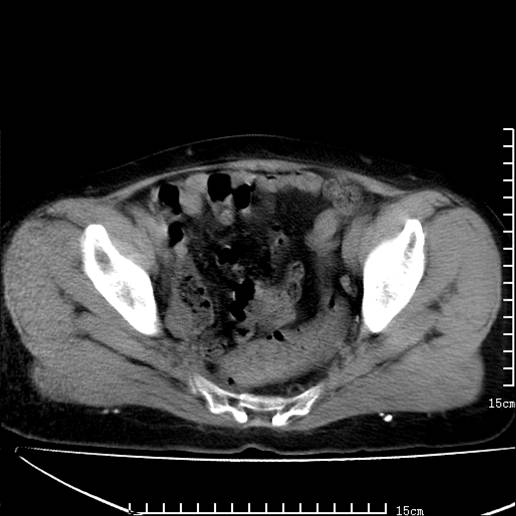

以下是引用pujunzhi在2008-5-30 15:31:00的发言:[br]异位肾—盆腔肾。当看到肾窝无肾脏时,要想到孤立肾和异位肾,异位肾最常见是盆腔肾,偶见胸腔,易误认为肺占位,只要想到就不会漏诊。建议增强扫描。